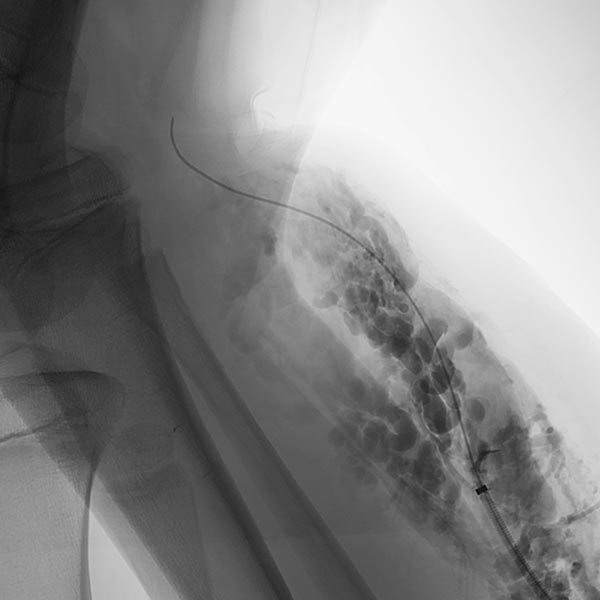

Die Phlebographie nach Direktpunktion des venösen Malformationsanteils zeigt eine großlumige Drainagevene, die in der Kniekehle mit der V. poplitea kommuniziert. Diese muss zunächst verschlossen werden, da sonst das Sklerosierungsmittel darüber abfließen könnte und potentiell eine Thrombose der tiefen Leitvenen des Beins (und eine Lungenembolie) verursachen könnte. Zudem besteht grundsätzlich ein erhöhtes Thrombembolierisiko bei der Patientin, dass durch den Verschluss deutlich vermindert werden kann.

Dazu wird zunächst über einen Einführungsdraht eine großlumige Einführungsschleuse vorgebracht, die zum Einführen der Laserfaser dient. Dieser wird über die Vene bis zum Kommunikationspunkt in der Kniekehle vorgeschoben.

Durch diese Schleuse wird eine Laserfaser zur endovaskulären Lasertherapie vorgeführt. Durch die Erhitzung des Laserstrahls kommt es zu einer massiven Reizung der Venenwand, die sich anschließend sehr schnell verschließt. Um die Laserspitze kommt es sofort zur Thrombusbildung (weiß, da als Kontrastmittelaussparung sichtbar).

Nach Verschluss durch die Laserfaser und Anspritzen über die zurückgezogene Schleuse kommt es nicht mehr zu einem Abstrom des Kontrastmittels über die Kommunikationsvene, die erfolgreich verschlossen ist. Es kontrastiert sich nur noch die venöse Malformation. Diese ist jetzt bereit zur Sklerosierungsbehandlung, da dieses nicht mehr abfließen kann.